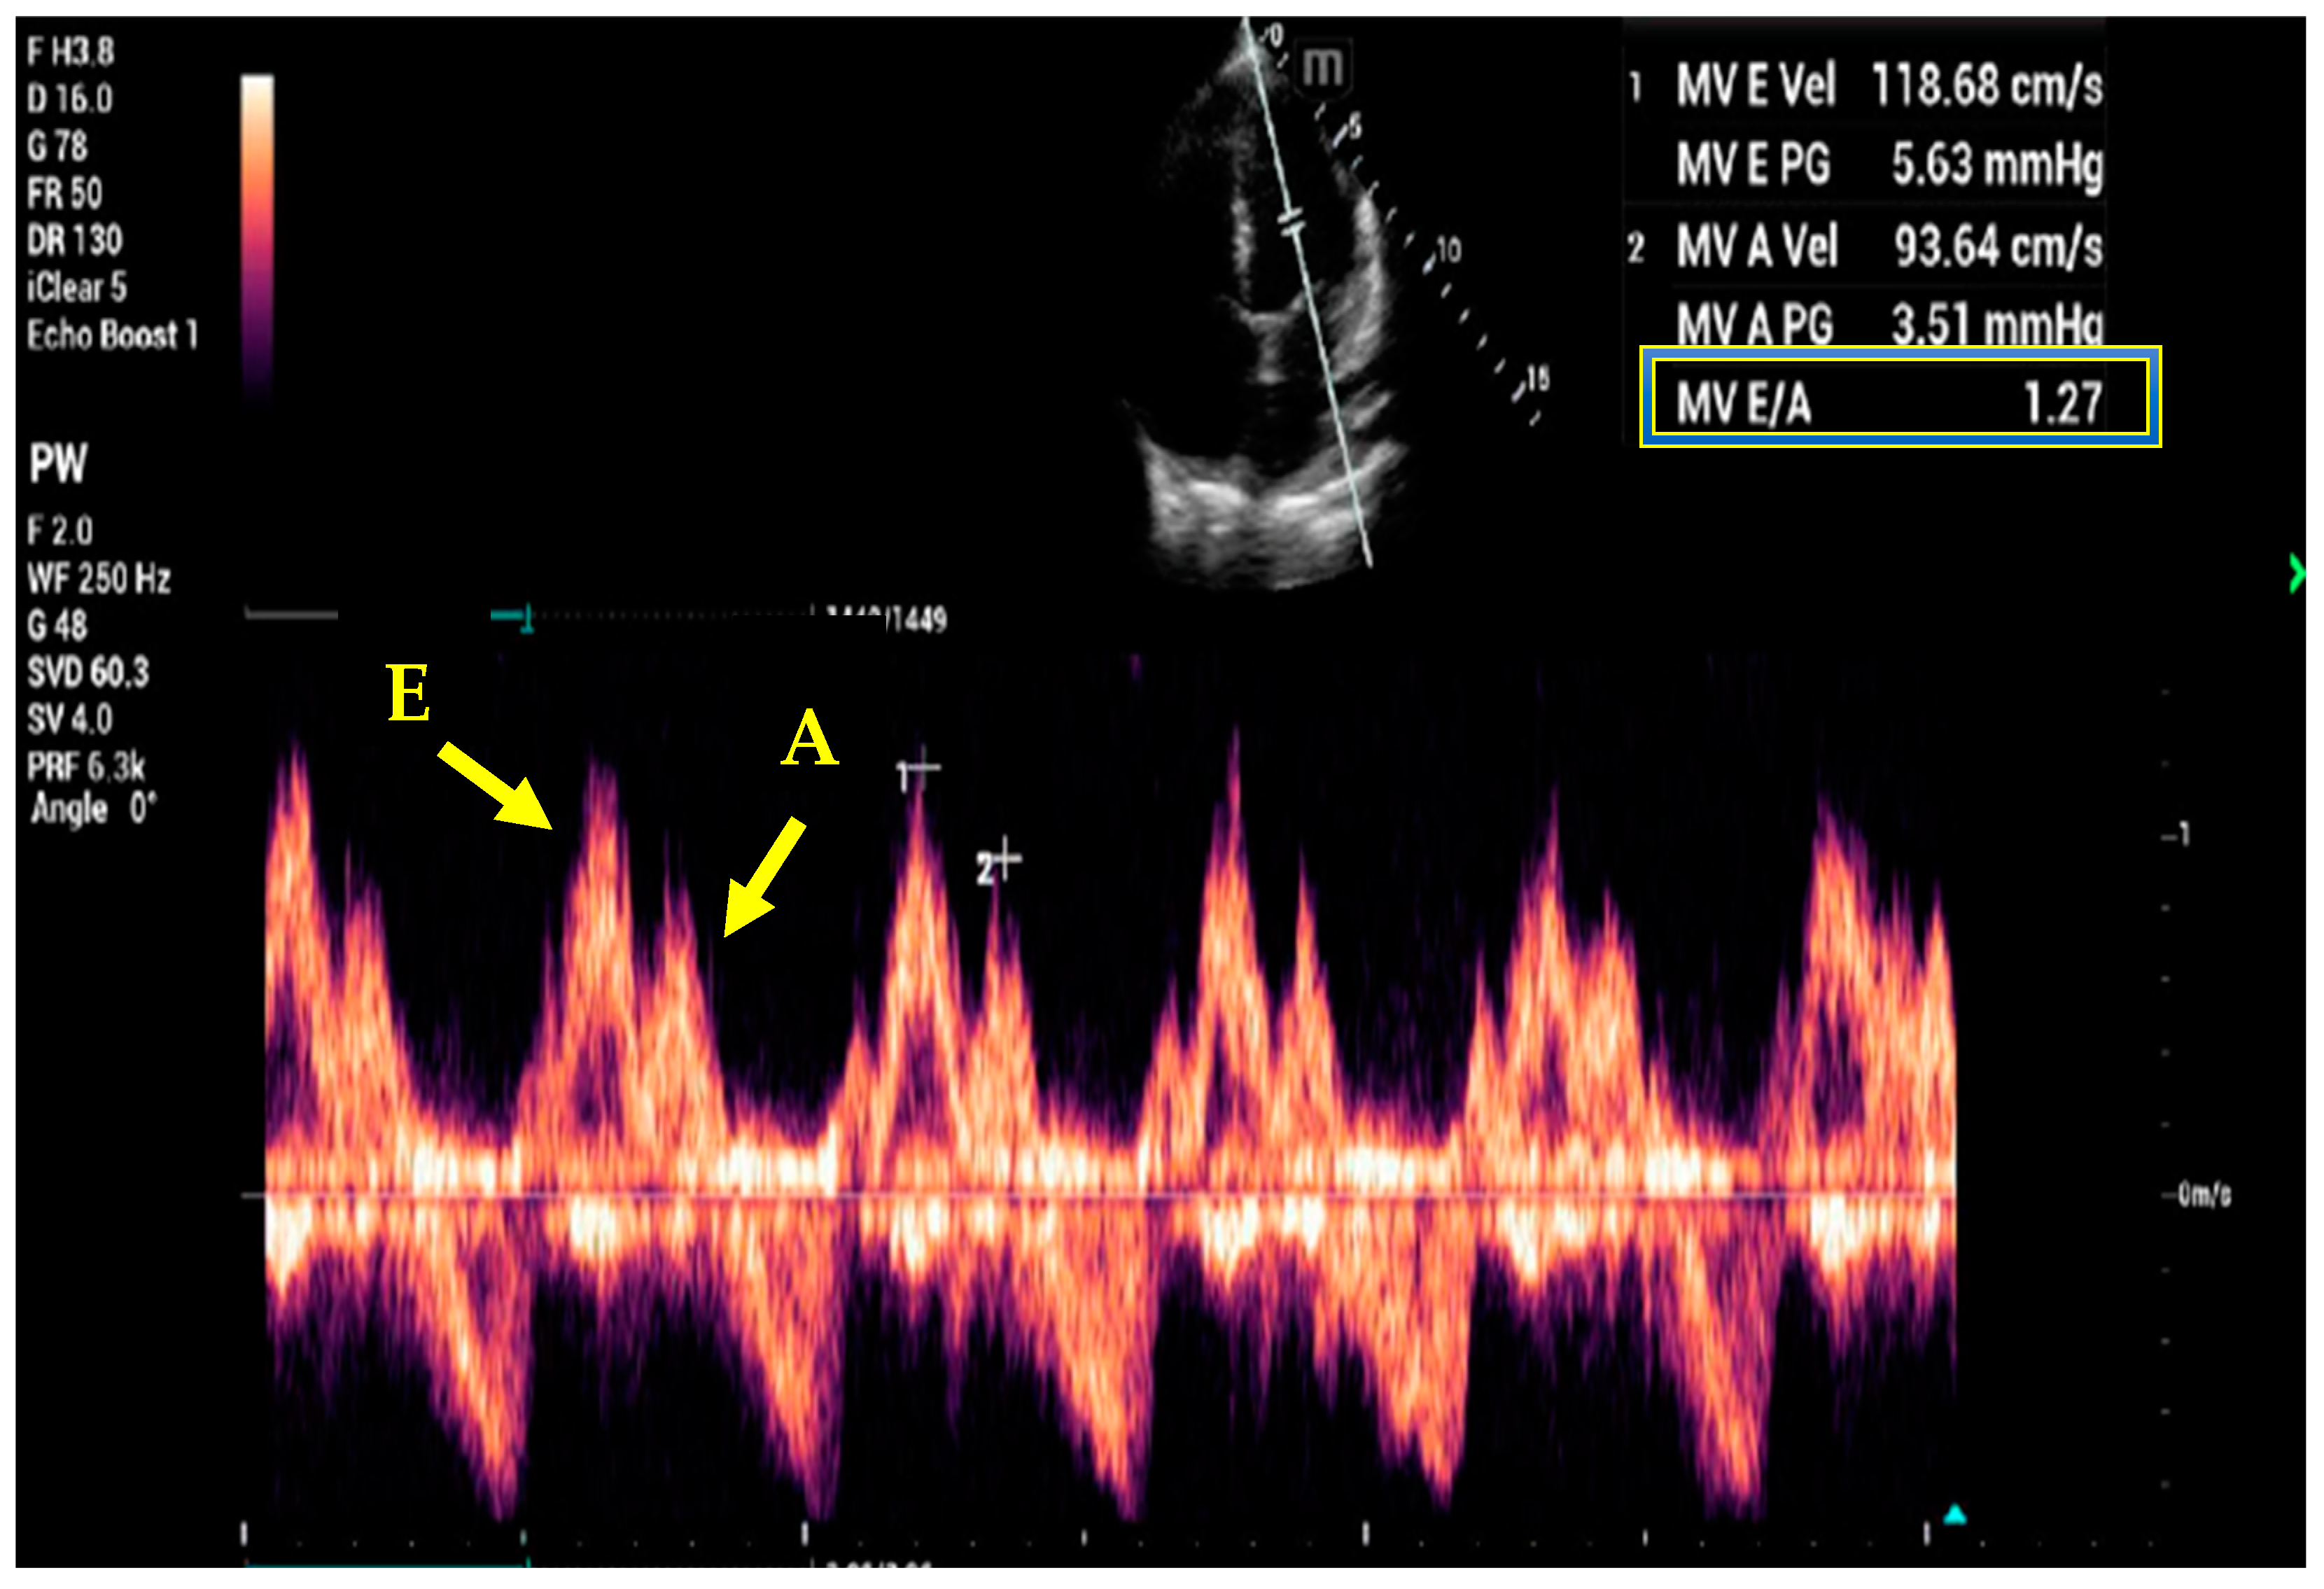

7. Basic and Advanced Echocardiography

- Kim, J.S.; Yang, J.W.; Yoo, J.S.; Choi, S.O.; Han, B.G. Association between E/e ratio and fluid overload in patients with predialysis chronic kidney disease. PLoS ONE 2017, 12, e0184764. [Google Scholar] [CrossRef] [PubMed]

- Nagueh, S.F.; Middleton, K.J.; Kopelen, H.A.; Zoghbi, W.A.; Quinones, M.A. Doppler tissue imaging: A noninvasive technique for evaluation of left ventricular relaxation and estimation of filling pressures. J. Am. Coll. Cardiol. 1997, 30, 1527–1533. [Google Scholar] [CrossRef]

- Nagueh, S.F.; Smiseth, O.A.; Appleton, C.P.; Byrd, B.F., 3rd; Dokainish, H.; Edvardsen, T.; Flachskampf, F.A.; Gillebert, T.C.; Klein, A.L.; Lancellotti, P.; et al. Recommendations for the Evaluation of Left Ventricular Diastolic Function by Echocardiography: An Update from the American Society of Echocardiography and the European Association of Cardiovascular Imaging. J. Am. Soc. Echocardiogr. 2016, 29, 277–314. [Google Scholar] [CrossRef]

- Lanspa, M.J.; Gutsche, A.R.; Wilson, E.L.; Olsen, T.D.; Hirshberg, E.L.; Knox, D.B.; Brown, S.M.; Grissom, C.K. Application of a simplified definition of diastolic function in severe sepsis and septic shock. Crit. Care 2016, 20, 243. [Google Scholar] [CrossRef]

- La Via, L.; Dezio, V.; Santonocito, C.; Astuto, M.; Morelli, A.; Huang, S.; Vieillard-Baron, A.; Sanfilippo, F. Full and simplified assessment of left ventricular diastolic function in covid-19 patients admitted to ICU: Feasibility, incidence, and association with mortality. Echocardiography 2022, 39, 1391–1400. [Google Scholar] [CrossRef]